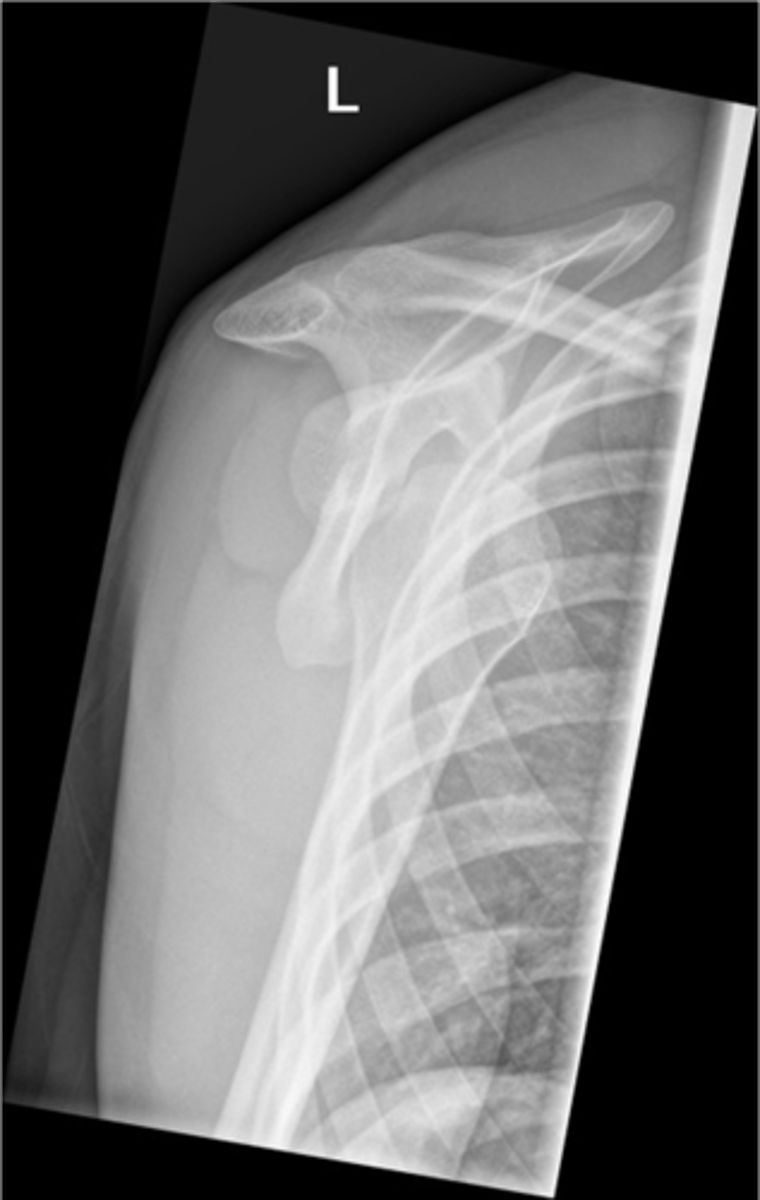

Condition: anterior GHJ dislocation via a Y-view -- makes dislocations MUCH more obvious

What is this image depicting? What view is it?